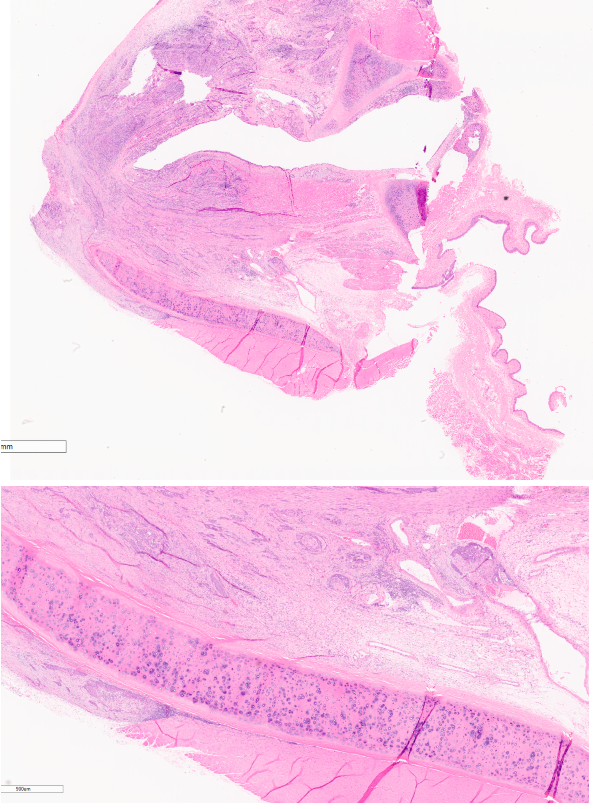

Identify this structure:

A

Viral papilloma

This is from the skin of the left elbow, provide a morphological diagnosis for this mass.

skin mass, left elbow: viral papilloma, exophytic